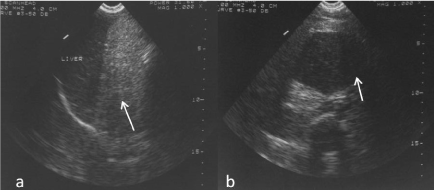

On ultrasound examination, it was found that whole of the abdomen was filled with an echogenic mass. The mass also extended into the pelvis. In addition, a well-defined hypoechoic SOL was seen in the umbilical region (Figure 1). Visualization of other organs was quite difficult. Grossly liver and gall bladder appeared normal though displaced laterally. Bilateral kidneys and spleen showed no gross abnormality. There was no evidence of free fluid. Retroperitoneal area could not be visualized.

Figure 1. a) Large echogenic mass in abdomen on US. Liver grossly normal, b) Well defined hypoechoic mass seen in the umbilical region on US.